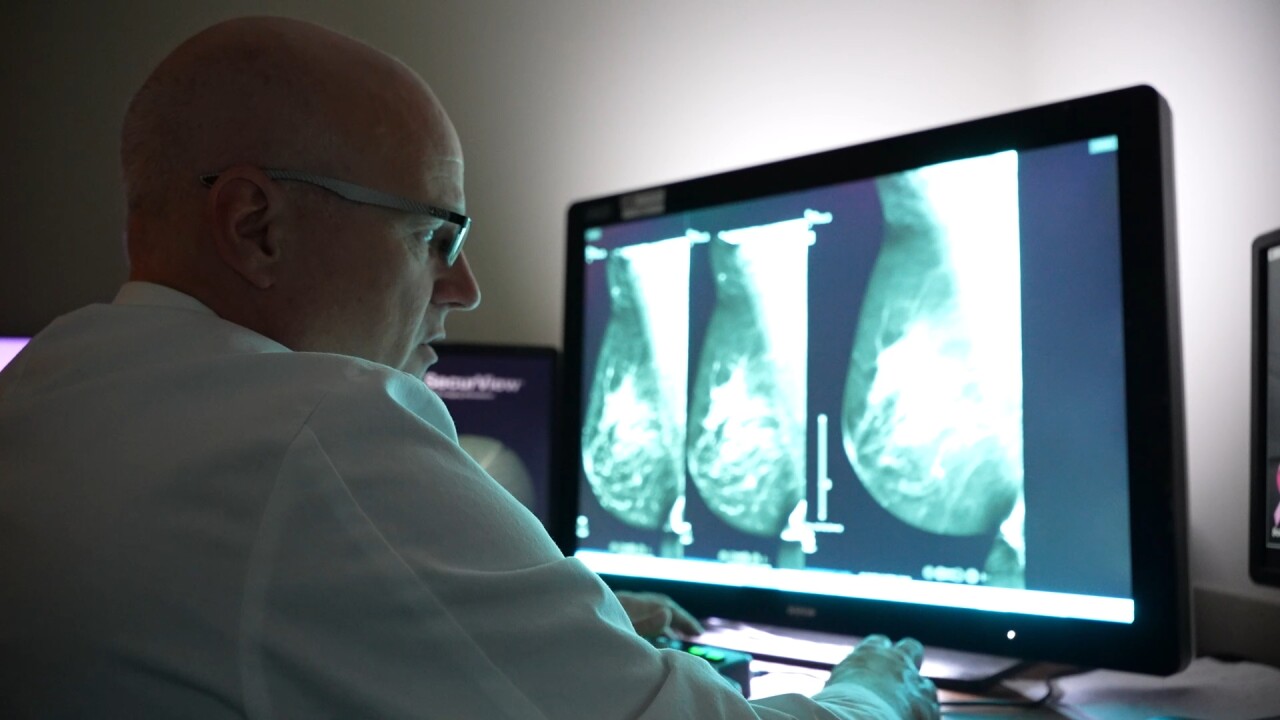

Dr. Troy Graybeal with Billings Clinic says the dye highlights areas of concern that might otherwise blend into dense tissue.

“Basically, what it does is it subtracts a lot of the ‘busy-ness’ of the breast tissue,” he said. “Cancers and lesions can be obscured by the breast tissue. This is a tool that helps us see through that.”

Graybeal knows the emotional toll of delivering tough diagnoses but believes this new tool will help detect cancers earlier and save lives.